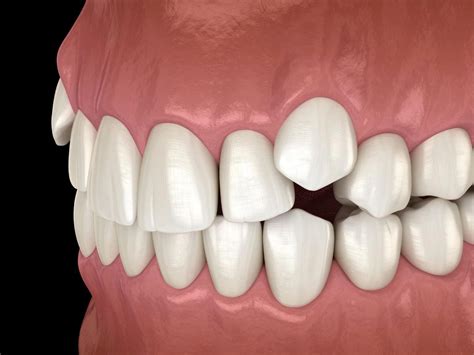

What Exactly Is an Impacted Canine Tooth?

An impacted canine tooth occurs when the tooth is prevented from erupting into its proper position in the dental arch. This often happens because the tooth is blocked by other teeth, the jawbone is too small, or there is an abnormal growth path. The maxillary (upper) canine is the second most common tooth to become impacted, following third molars (wisdom teeth). While it might seem like a minor inconvenience, leaving an impacted tooth untreated can lead to serious complications, including the absorption of the roots of neighboring teeth or the development of cysts.

• Visible gaps where the canine should be, or teeth appearing crowded in that area.

• The appearance of the canine erupting in the wrong place, such as in the roof of the mouth or high up near the lip.